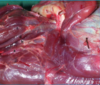

larynx